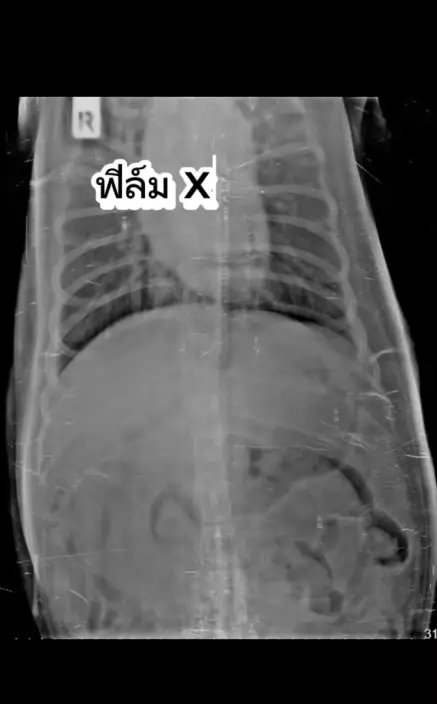

病情逐漸穩定不需手術 仍需觀察排出龜殼

幸運地是,Mo的狀況於數日後逐漸穩定,能成功排出部分排泄物,腸胃氣體也明顯減少,無嘔吐症狀且能正常進食,初步排除腸道完全阻塞的可能。飼主為求安全將X光片發給其他獸醫會診,皆認為不需手術。惟幼龜殼仍留在體內,需待Mo慢慢排出,獸醫已開出消化藥協助。